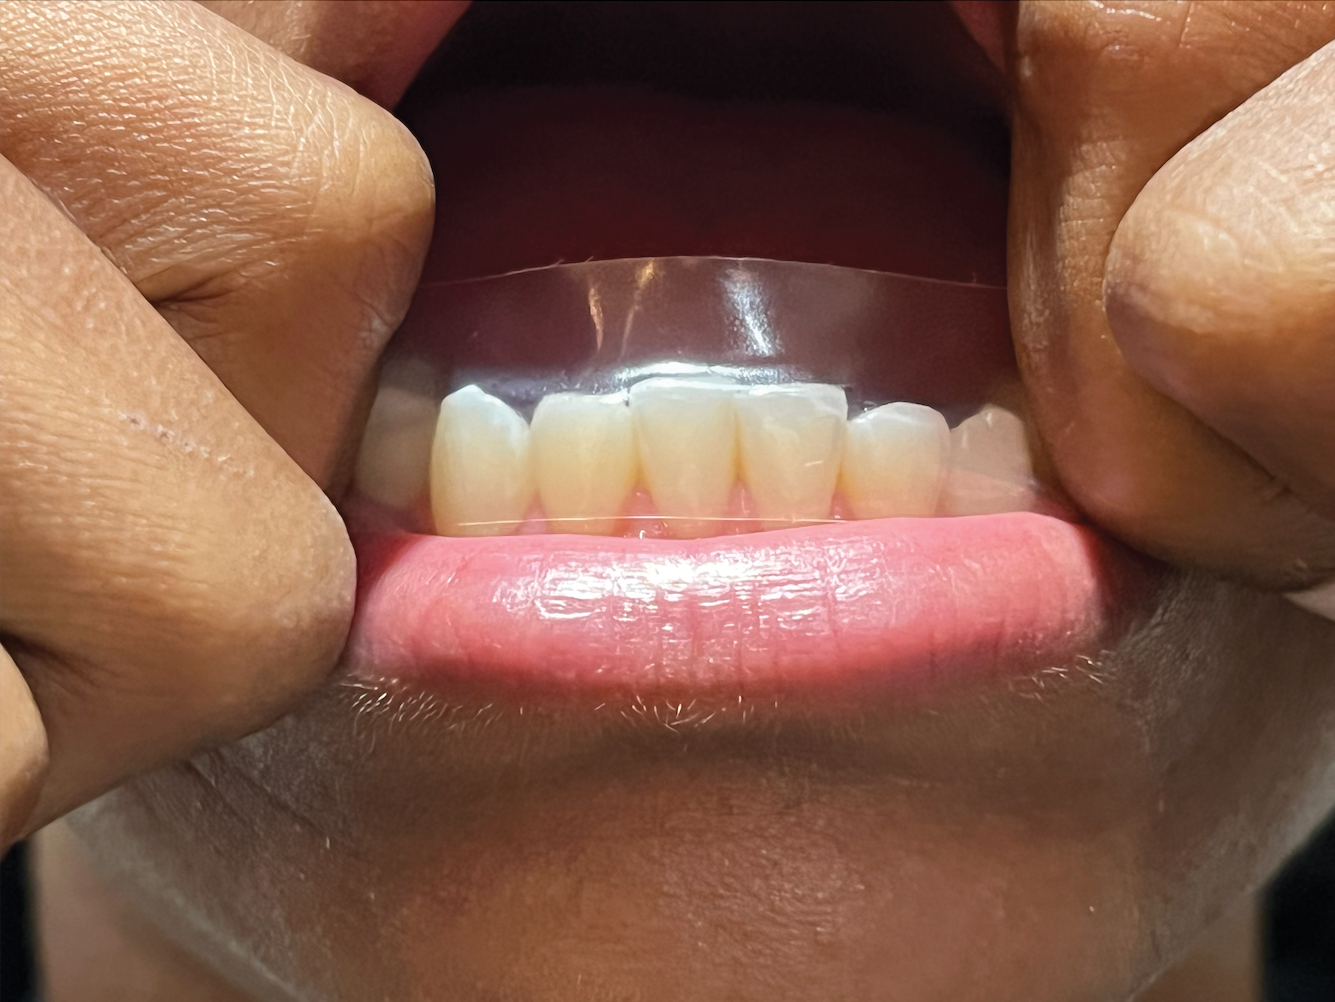

(9.) Dissolvable whitening strips are a desirable option for use as a patient motivator and adjunctive therapy.

Figure 9

The patient plays a vital role in periodontal disease prevention and management. Therefore, the clinician must allot sufficient time to oral health education during each appointment to ensure that patients have the knowledge they need to function as an effective co-therapist for their oral healthcare needs. It can be difficult to keep patients motivated to perform their home care routines. However, patients who whiten their teeth have been found to be more compliant with treatment plans and regularly scheduled appointments. Approximately $1.4 billion is spent each year on over-the-counter whitening products, but patients should be getting whitening recommendations from their providers. Clinicians can help patients stay motivated to maintain their oral health by recommending the use of whitening strips embedded with hydrogen peroxide. Patients then get the benefit of a white smile and the therapeutic benefit from the antimicrobial effect as a result of the oxygenating action of the hydrogen peroxide. Recommended products are formulated with 10% hydrogen peroxide, which is one of the highest over-the-counter percentages available to consumers. The strips are also dissolvable within just 15 minutes, making them a desirable option for use as a patient motivator and adjunctive therapy (Figure 8 through Figure 10). Examples include LumiSmile® White Dissolving Strips (Oral ProCare) and ACCLEAN Professional Dissolvable Teeth Whitening Strips (Henry Schein), for example.